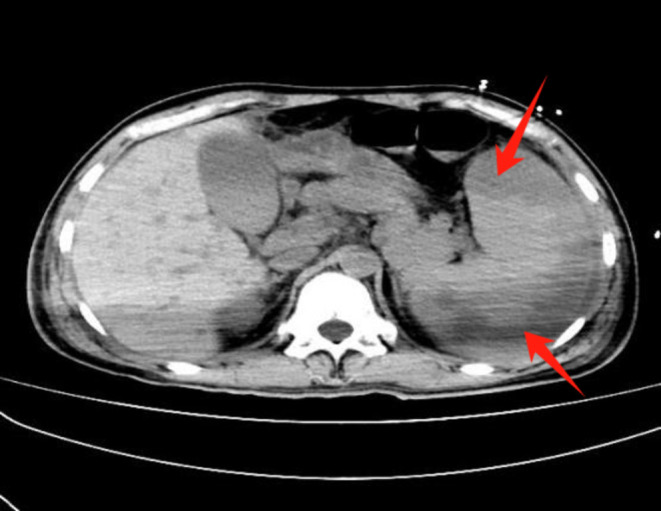

Yersinia pseudotuberculosis is a Gram-negative bacterium of the family Yersiniaceae, primarily transmitted via the gastrointestinal tract. Progression to sepsis is uncommon, and the combination of septic shock and splenic infarction is exceedingly rare. We report a 40-year-old male who initially presented with fever, abdominal pain, and distension, which rapidly progressed to sepsis and multi-organ dysfunction. Definitive diagnosis of Y. pseudotuberculosis infection was established by blood culture and metagenomic next-generation sequencing, supported by imaging evidence of splenic infarction. The patient was managed with stepwise antimicrobial regimens (including piperacillin-tazobactam, meropenem, levofloxacin, linezolid, and daptomycin), plasma exchange, continuous renal replacement therapy, and organ function support. Following comprehensive treatment, the patient recovered and was discharged in stable condition. This case highlights the importance of considering Y. pseudotuberculosis in atypical sepsis presentations and demonstrates that timely diagnosis and multidisciplinary management are crucial to improving outcomes in such rare and life-threatening infections.